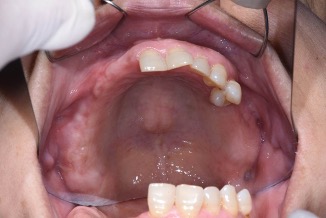

下顎植牙兩顆-林錫奎醫師

下顎植牙兩顆

治療中

安裝後